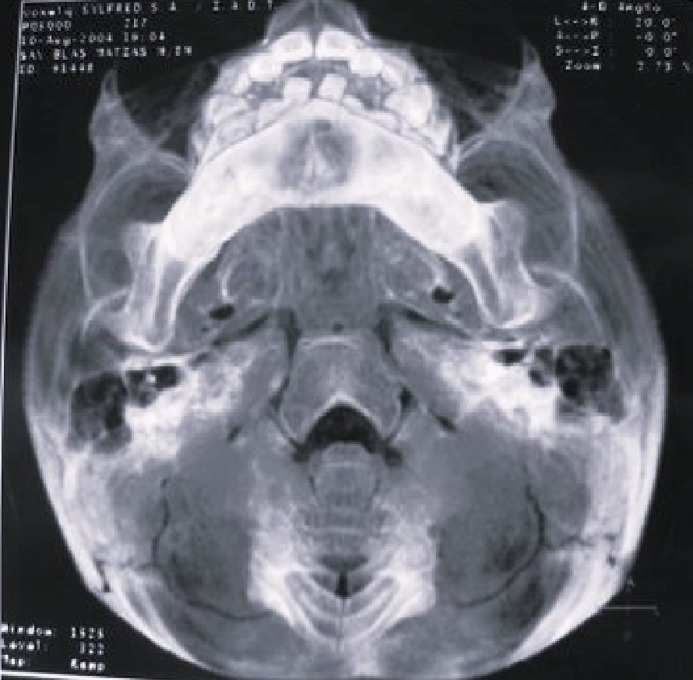

Materials and method: Clinical and radiographic examinations were used to evaluate 95 patients diagnosed with LCH, aged 0 to 16 years, who were referred to the Department of Comprehensive Pediatric Dentistry at the School of Dentistry, University of Buenos Aires. Clinical histories were prepared and informed consents obtained. Lesions were diagnosed by observation, palpation and biopsies, and grouped according to affected tissues into bone, mucosal, and bone-mucosal.

Results: 42.1% presented oral lesions, and in 14.73%, these lesions were the first manifestation of LCH. Ninety percent presented only bone lesions, while the remaining 10% presented bone-mucosal and mucosal lesions. In the single-system subtype, 52.5% presented bone lesions. In the multisystem subtypes (with or without risk organs), all three types of lesions were found. The association between age at which LCH was diagnosed and oral tissue involvement showed that bone-mucosal lesions occur in young children (average age 1.4 years) diagnosed with multisystem LCH. Oral mucosa was only affected in reactivations of the disease.

Conclusions: A high frequency of oral lesions was observed, which were sometimes the first manifestation of the disease, most often affecting bone tissue. Dentists can play an active role in the initial diagnosis of the disease.